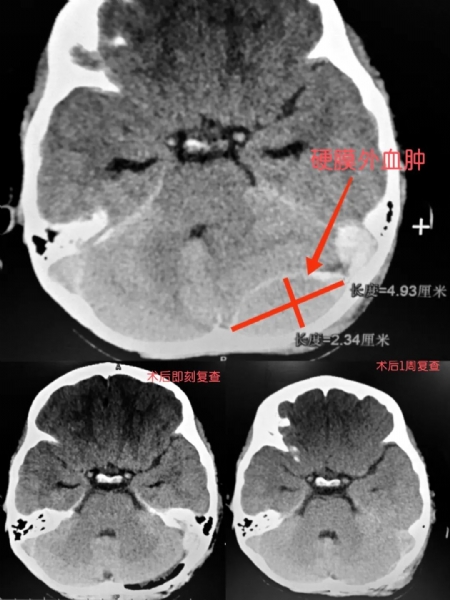

患儿为7岁的学龄儿童,在家玩耍时摔倒头枕部,伤后患儿头痛,但无其他症状,未就医。外伤约16小时后患儿出现恶心、呕吐,遂来诊,查头颅CT示左枕骨骨折并伴有左枕部跨静脉窦部硬膜外血肿,因血肿位置特殊,一旦处理不当便会引起灾难性的静脉窦大出血,从而危及生命。入院时因出血量不多,不具有手术指征,故决定采取保守治疗。同时,医生根据临床经验,考虑到此硬膜外血肿属于非稳定血肿,采取了动态复查颅脑CT并严密观察患儿病情变化。在入院的第二天凌晨2点左右,医务人员发现患儿恶心、呕吐加重,同时意识状态转差,考虑可能由患儿颅内血肿增加所导致,经过复查头颅CT证实出血量呈进行性明显增多趋势,继续观察有增加脑疝风险,须果断手术治疗。于是紧急在全麻下行枕部跨横窦硬膜外血肿清除术。在神经外科医护团队、手术麻醉科团队和ICU团队的密切协作之下,患儿顺利的度过了危险期。目前,患儿恢复良好,言语表达流畅,思维敏捷,四肢活动良好,未出现脑功能后遗症。术后1周小朋友便能下床活动,在家长的引领下,给科室医护人员送来了锦旗和一捧别具心裁的文具花束,表达对医护叔叔阿姨们的谢意。